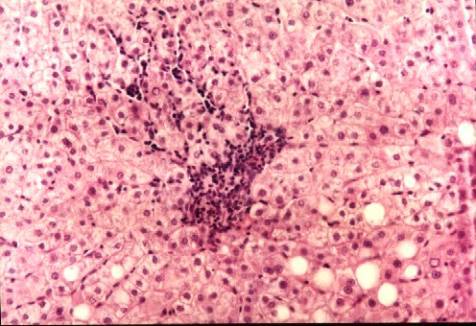

坏死(necrosis)是以酶溶性变化为特点的活体内局部组织细胞的死亡。坏死可因致病因素较强而直接导致,但大多数由可逆性损伤发展而来,其基本表现是细胞肿胀、细胞器崩解和蛋白质变性。炎症时,坏死细胞及周围渗出的中性粒细胞释放溶酶体酶.可促进坏死的进一步发生和局部实质细胞溶解,因此坏死常同时累及多个细胞。